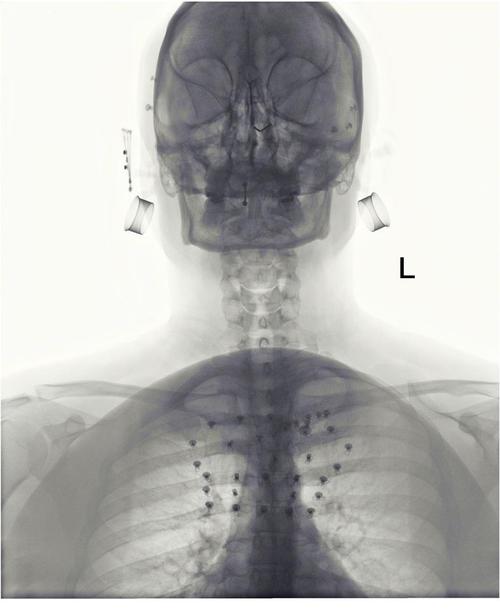

Mocne. :D Lubię badać pochodzenie różnych obrazków za pomocą tineye.com. Tego gościa z rozwalonym dołem twarzy znalazłem tu http://www.onlinejets.org/text.asp?2009/2/1/51/44685. Ponoć była to próba samobójcza z użyciem pistoletu. Można czasem też w ten sposób odnaleźć oryginalne obrazki, mając do dyspozycji tylko przeróbkę. ;)